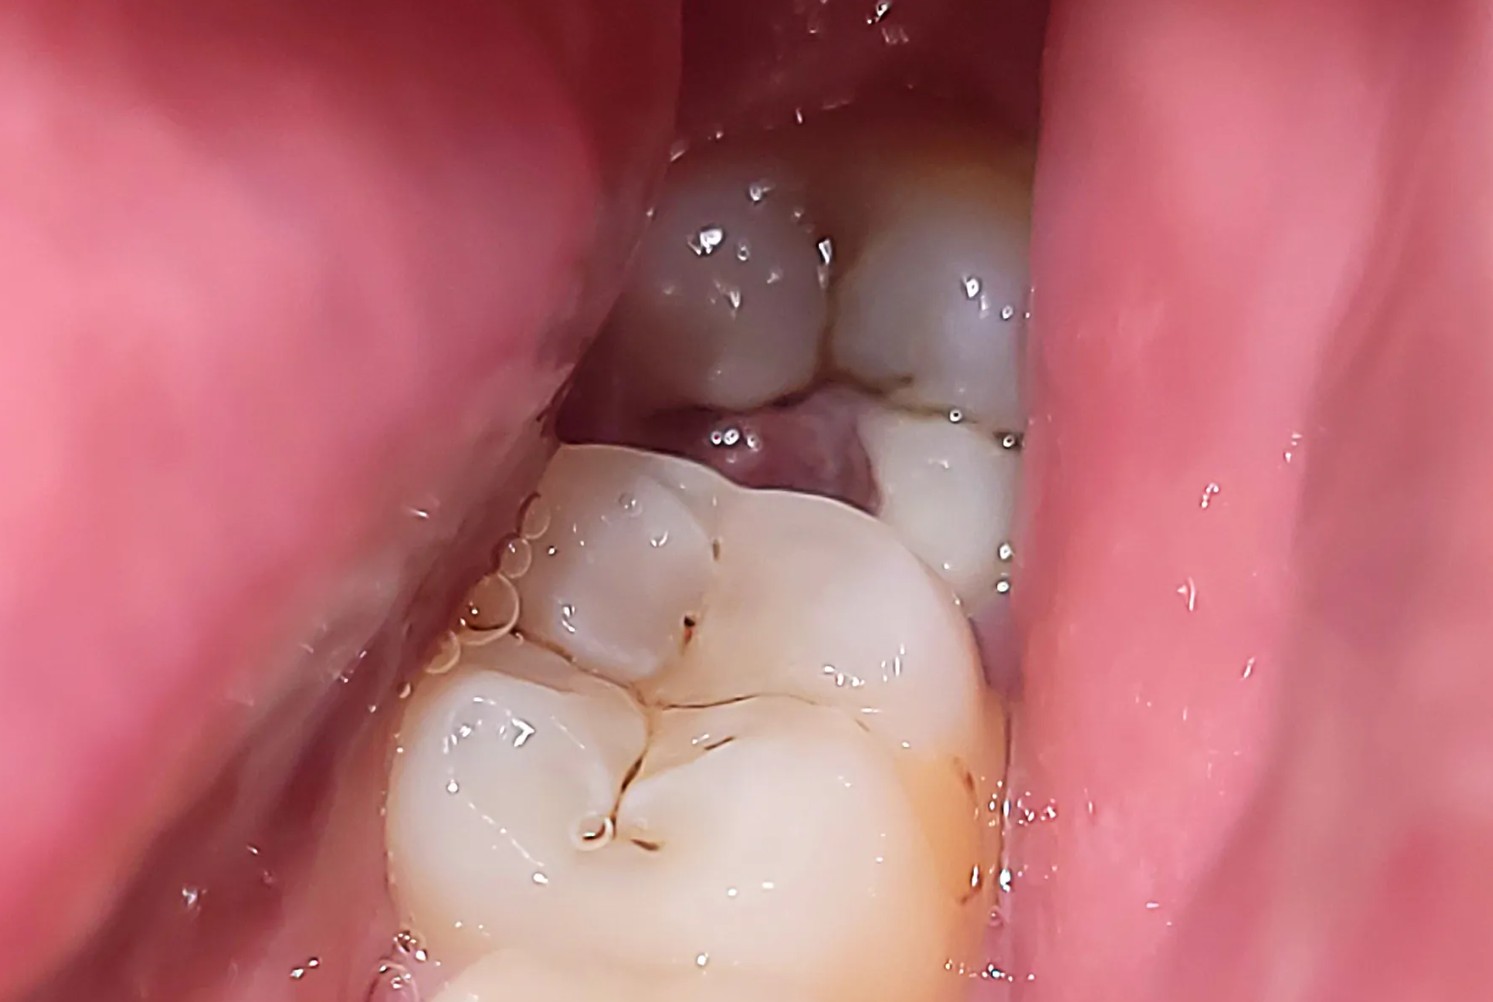

- Sưng lợi: Lợi vùng răng hàm cuối cùng hơi phồng lên, đỏ, hoặc dễ chảy máu khi chải răng.

Khi răng khôn không mọc đúng hướng hoặc mọc ngầm, nó có thể gây ra hàng loạt vấn đề răng miệng, bao gồm:

- Sưng nướu hoặc viêm quanh thân răng: Nướu vùng răng khôn sưng đỏ, có thể tụ mủ hoặc chảy dịch.